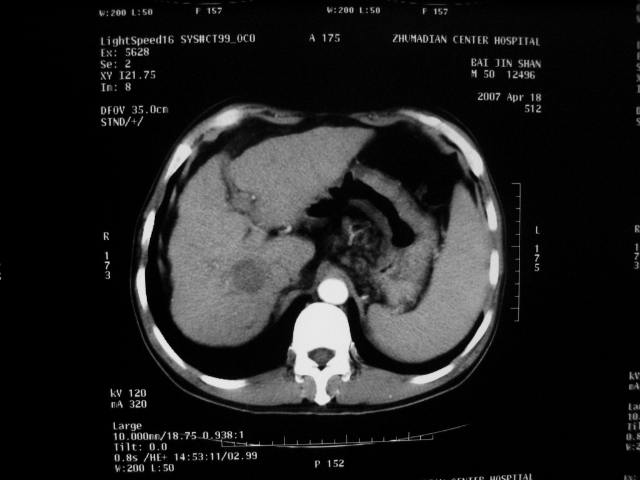

标题: CT7751:病人,50岁,肝硬化多年,行CT三期扫描 [打印本页]

标题: CT7751:病人,50岁,肝硬化多年,行CT三期扫描

动脉期病灶见轻度强化,考虑肝癌可能性大。

动脉期轻度强化 考虑 肝右叶小肝癌可能性大

1、肝右叶低密度灶考虑肝癌

2、肝硬化

肝硬化、脾大,静脉曲张,肝右叶低密度灶,增强无明显强化,还是考虑肝癌可能性大,建议结合afp检查。

考虑肝硬化,脾大,静脉曲张,肝右叶低密度灶,右肝癌可能性大。

肝硬化一定会有肝癌吗,没有ct值吗,就是一个囊肿

肝癌分为肝细胞性和胆管细胞性,从强化表现来看,确切地说应是胆管细胞癌.